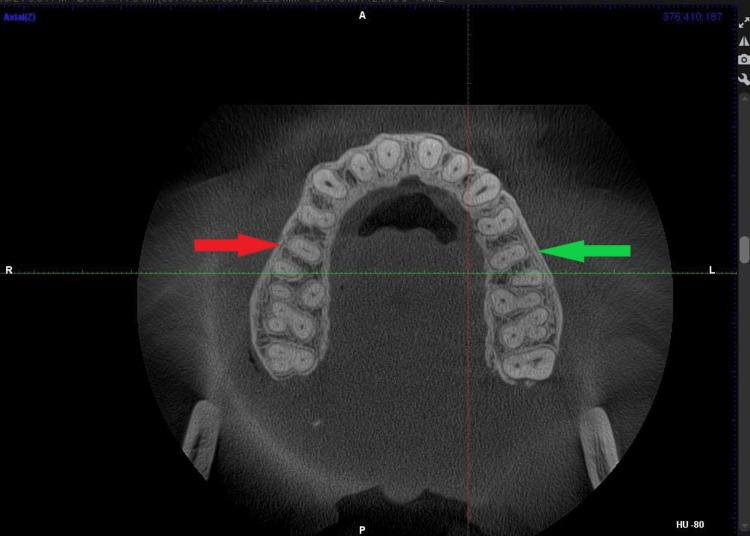

背景与目的 全面了解根管形态及其解剖变异对于根管治疗(RCT)的成功至关重要。未被识别的变异可能导致清洁、塑形和充填不彻底,从而可能导致治疗失败。本研究旨在使用锥形束计算机断层扫描(CBCT)评估上颌第二前磨牙(Mx2P)根管形态类型的频率和分布及其与性别的关系。

材料与方法 本回顾性横断面研究分析了18至65岁患者中384例完全发育、未经治疗的Mx2P的CBCT扫描图像。排除有修复体、先前接受过根管治疗、严重龋齿、骨折、牙根粘连或牙髓钙化的牙齿。使用Carestream Dental Imaging Software 3D Module v2.4根据Vertucci分类系统对根管形态进行分类。使用卡方检验进行基于性别的比较。

结果 纳入了219例患者(114例男性(52.1%),105例女性(47.9%))的扫描图像,平均年龄为42.35±13.79岁。最常见的根管形态为Vertucci I型(n = 240,62.5%),其次是II型(n = 96,25.0%)、IV型(n = 30,7.8%)、VI型(n = 3,0.8%)、VII型(n = 3,0.8%)、III型(n = 7,1.8%)、V型(n = 4,1.0%)和VIII型(n = 1,0.3%)。未发现根管形态与性别之间存在统计学显著关联(p = 0.915)。

结论 Vertucci I型是上颌第二前磨牙最常见的根管形态。研究结果强调了使用CBCT进行全面影像学评估以识别解剖变异对于有效的根管治疗计划的重要性。